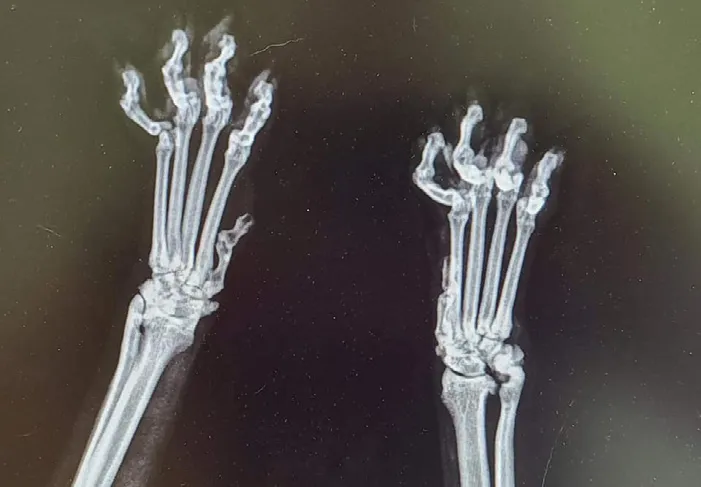

Chapman reached out to several vets regarding Phoebe’s declaw. Assessments and X-rays revealed astounding results.

“This poor girl was declawed at an early age, and now after living with a botched declawed surgery for almost 10 YEARS, we can clearly see advanced arthritis and trauma in her paws and wrists from a quick X-ray. Her constantly nimble ‘high heel’ shuffle is due to potential bone fragments left in the tips of her toes from being declawed and the advanced wrist arthritis from not walking properly for years. “Well, no wonder my jerk foster cat wants to bite everyone sporadically!”